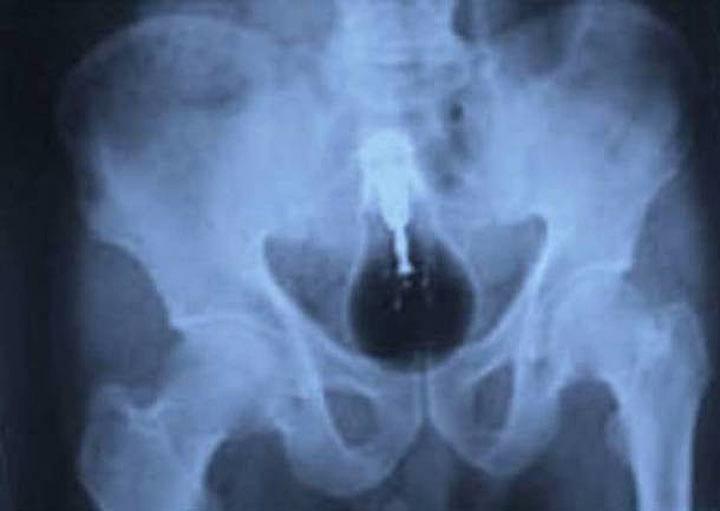

13. Этот мужчина отрицал произошедшее. Но факты — вещь упрямая.